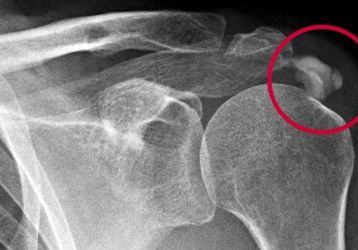

Вывих плеча: причины травм, симптомы и варианты лечения

Вывих плечевого сустава(плеча): признаки, причины, диагностика. Привычный вывих плечевого сустава. Первая помощь и методы лечения травм плечевого сустава.